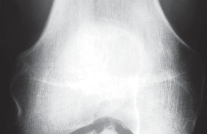

DEFINITION Chapter2 Open Reduction and Internal Fixation of the Symphysis Michael S. H. Kain and Paul Tornett…